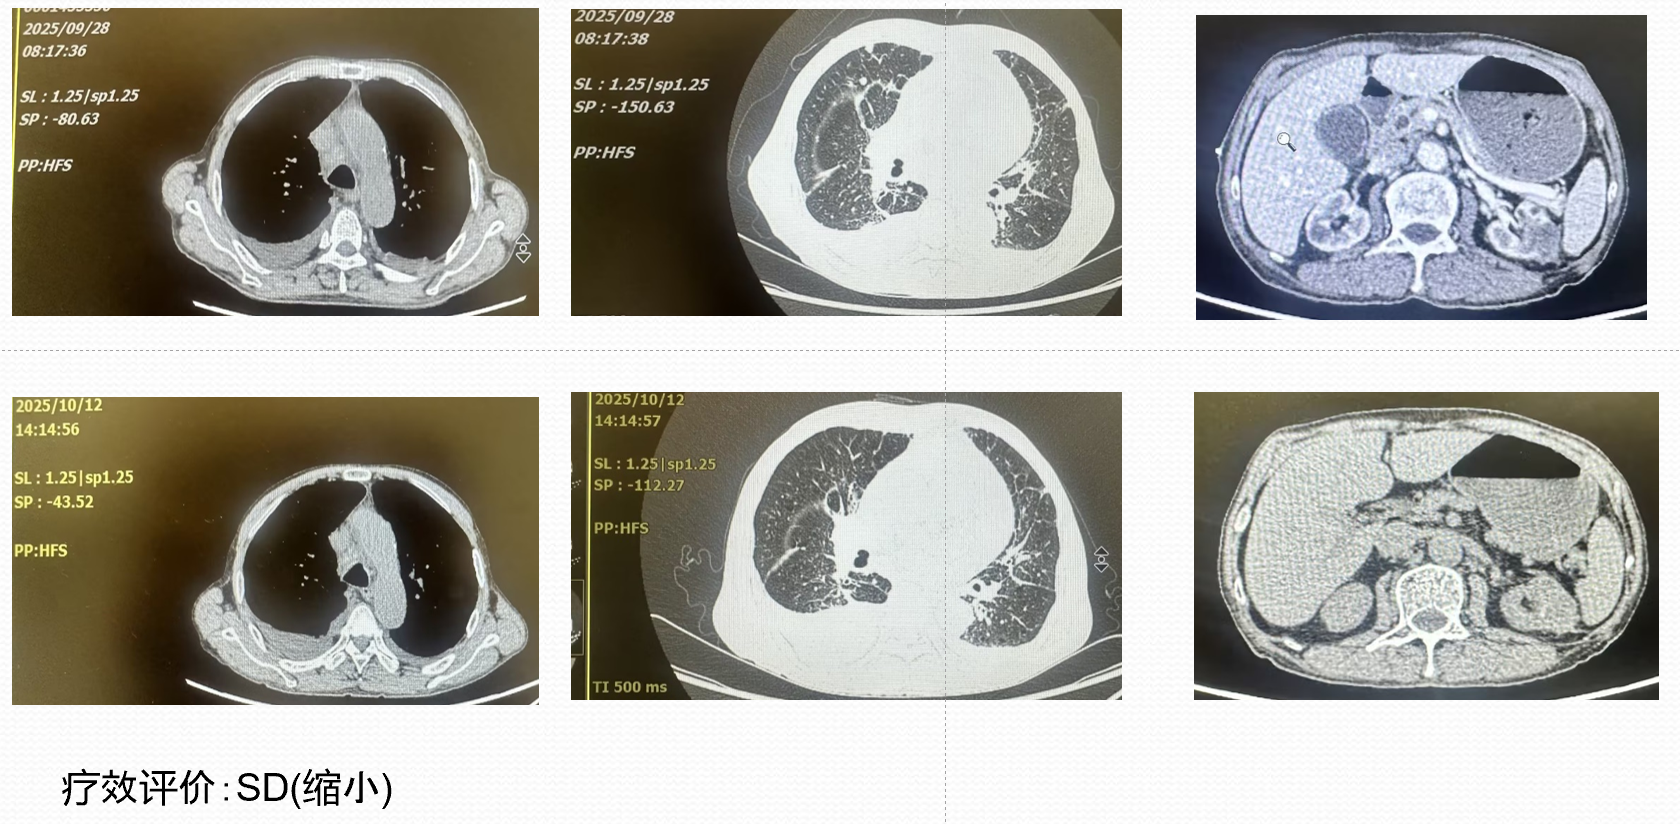

• 2025-9-16胸腹部CT示:1.临床提示左肾肿瘤术后:目前左腹壁瘢痕影、瘢痕处强化不均,左肾上份稍低密度团块影,考虑肿瘤性病变,复发?其它?邻近左侧腹膜后强化结节影,转移?纵隔、右肺门、腹膜后增大、部分坏死,考虑转移;双肺多发小结节,部分转移可能。请结合;临床及外院旧片。2.右侧液气胸、肺组织压缩约40%,右侧胸腔置管影,右肺部分受压不张、强化尚均,合并其它待排;建议治疗后复查。3.肺气肿,双肺散在炎变、部分为慢性炎变。4.主动脉及冠状动脉壁钙化,气管内少许粘液。5.双侧胸膜增厚,左侧胸腔少量积液。6.肝右后叶小囊性灶,建议随诊。7.胆囊结石。8.双肾髮肿。9.前列腺强化不均,必要时结合MR平扫及增强检查。

• 2025-9-30行洛铂+地塞米松控制胸水,具体:地塞米松10mg及洛铂10mg胸腔灌注,胸腔灌注后拔除胸腔穿刺引流管。并口服培唑帕尼片800mg qd靶向治疗。

• 治疗 20 多天后患者出现气急、腹泻等症状,暂停培唑帕尼治疗,复查 CT 显示部分病灶缩小,但心包积液增多,行心包腔及双侧胸腔穿刺引流,病理提示心包转移,给予洛铂及地塞米松心包腔灌注,

• 2025-10-25培唑帕尼靶向治疗,减量为 600 毫克/天。